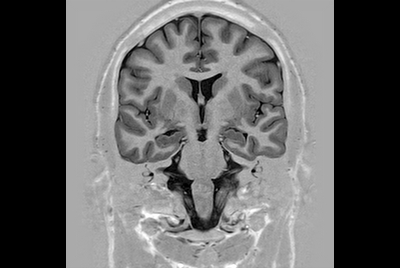

Brain overview